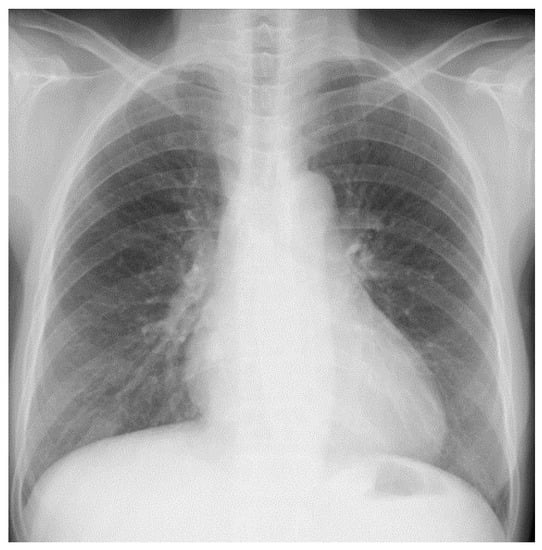

A Case of Mediastinal Tuberculous Lymphadenitis in a Chronic Dialysis Patient Diagnosed by Endobronchial Ultrasound-Guided Transbronchial Needle Aspiration (EBUS-TBNA)

2. Case